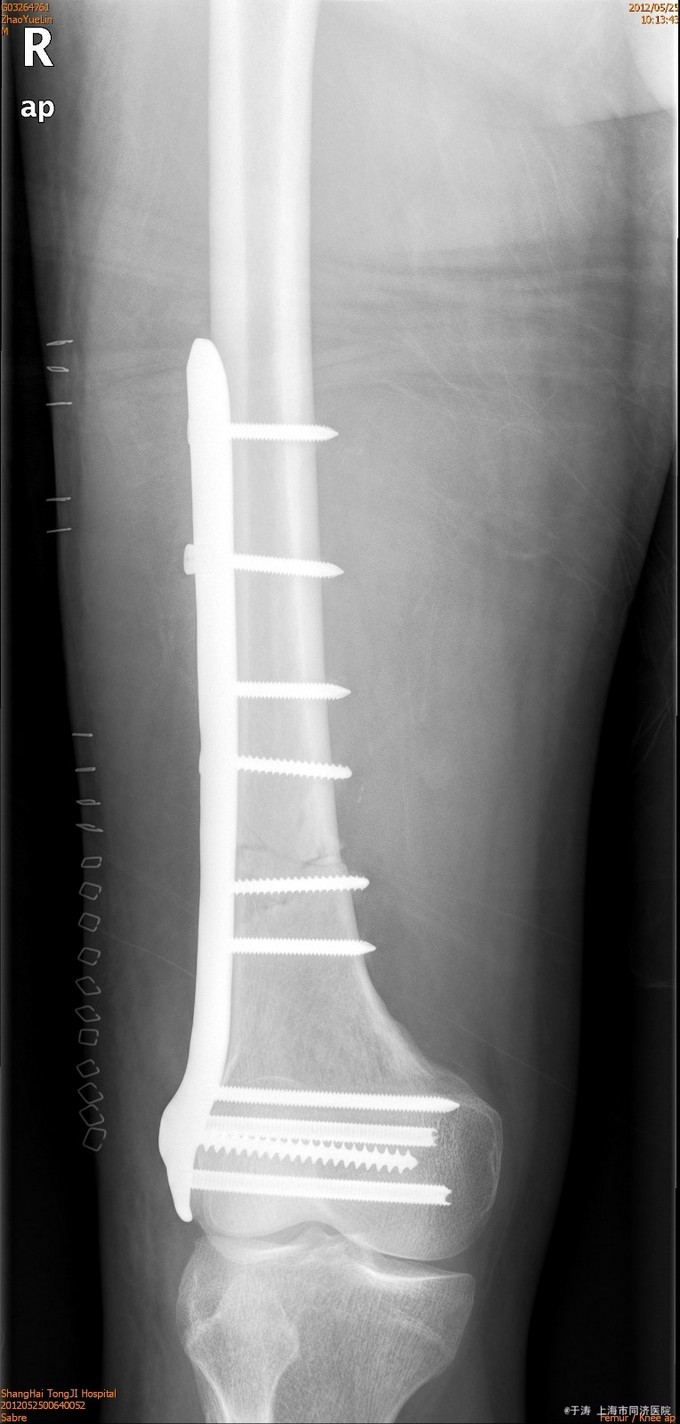

诊断为右股骨远端骨折,生命体征平稳后,行切开复位内固定术。

术后1年随访,功能良好,患者拒绝摄片和拔除内固定。对于股骨远端骨折,切开复位钢板内固定疗效可。